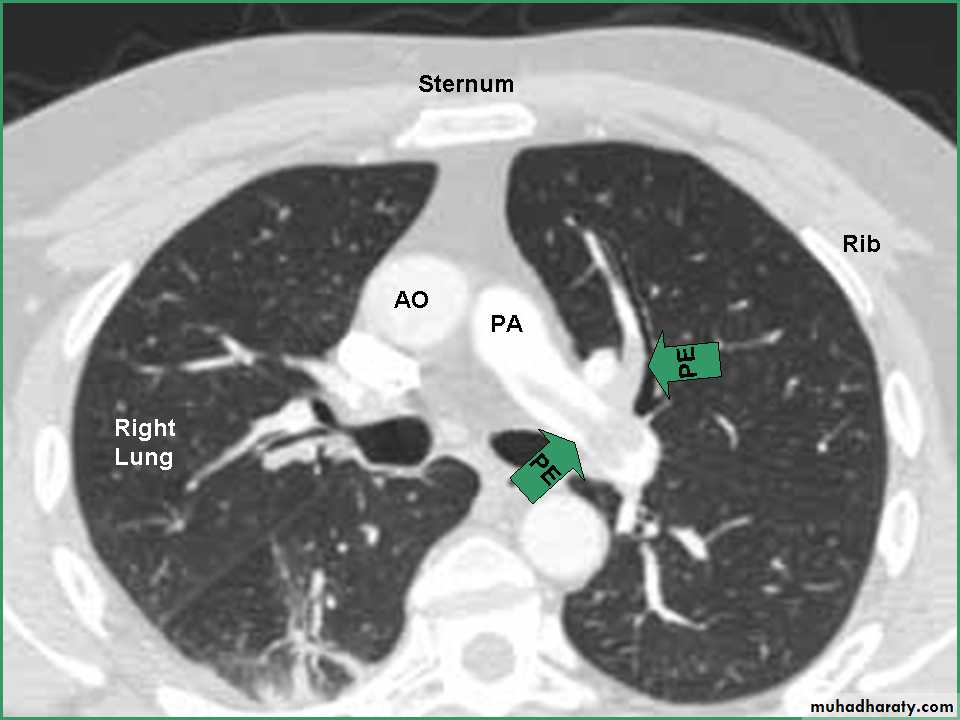

• CXR oligemia or linear or triangular consolidation,

• Pulmonary angiograms: filling defects or obstruction of pulmonary arterial branches.